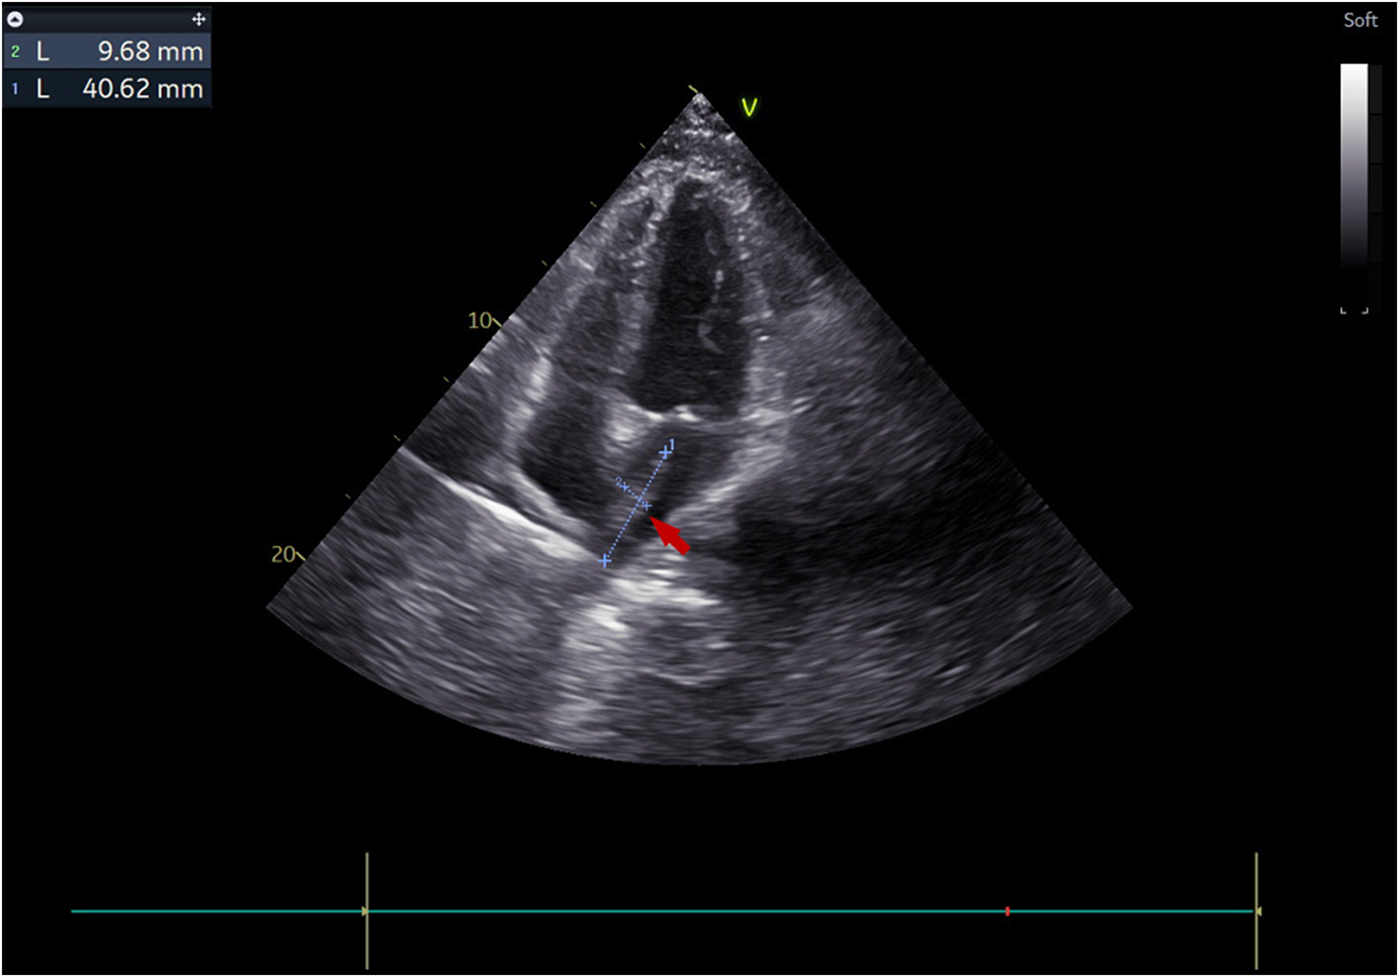

Figure 2

Transthoracic echocardiography visualized a 4 × 1 cm pedunculated vegetation (arrow) in the left atrium in the apical four-chamber view.

The treatment timeline for this patient is shown in (Figure 1). A 38-year-old male with a history of autoimmune lymphoproliferative syndrome (ALPS) and secondary hemophagocytic lymphohistiocytosis (HLH) underwent allo-HSCT on January 12, 2025. Post-HSCT course in the protective isolation unit was uneventful. Following isolation unit discharge on February 10, he developed persistent fever. Plasma metagenomic next-generation sequencing (mNGS) detected V. volvacea DNA (15 copies/μl). Oral voriconazole was initiated on the same day for suspected fungemia. On March 1, his fever escalated to 39°C. Repeat mNGS testing reveals a marked increase in fungal load (1,137 copies/μl). He was then diagnosed with IFIs and treated with intravenous amphotericin B and voriconazole starting March 3. Fever control was achieved in 2 days. On March 11, the peripheral blood fungal load reduced to 2 copies/μl. On March 15, the patient experienced a new-onset mid and lower back pain. A contrast-enhanced CT was performed to revel multiple emboli in the right parietal lobe of the brain and both kidneys. Transthoracic echocardiography (TTE) demonstrated a 4 × 1 cm left atrial vegetation arising from the right inferior pulmonary vein (RIPV) (Figure 2).